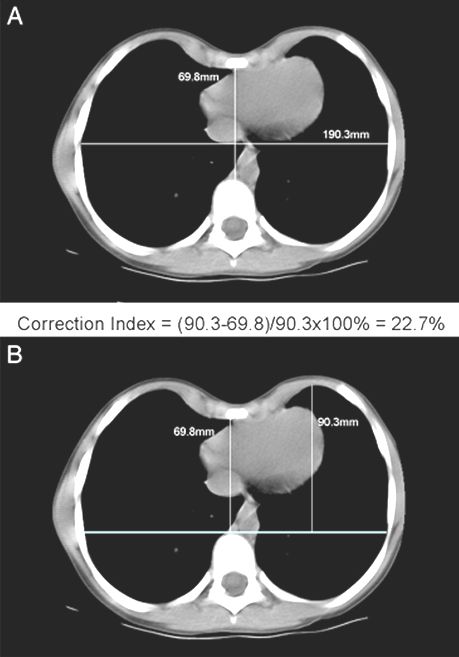

El Índice de Haller, el método estándar para valorar, la gravedad de pectus excavatum, depende de la anchura del tórax, y no evalúa la profundidad del defecto. Por lo tanto, se realizó un análisis de diagnóstico para evaluar la capacidad del HI para separar a los pacientes con pectus excavatum de controles sanos en comparación con un índice novedoso (INDICE DE CORRECCIÓN).

El índice de Haller demuestra superposición del 48% entre los pacientes normales y los que tienen pectus excavatum (gráfico). Sin embargo, el índice de corrección propuesto, separa perfectamente  las poblaciones normales de los afectados.

Indice de corrección (IC):  Se miden dos distancias:

1- la distancia mínima entre el esternón y la columna vertebral posterior como se utiliza para el índice de Haller, y

2- la distancia máxima entre la línea trazada por la columna vertebral anterior y el margen interno de la porción más anterior del pecho.

La diferencia entre las dos se divide por la segunda (x 100) para dar el porcentaje de la profundidad del pecho  que representa el defecto.

Ejemplo de la figura: índice de corrección = (90.369.8) / 90.3 X 100% = 22.7%.

Esta corrección separa la población de niños normales con los que tienen pectus excavatum.

Así los pacientes que tienen un IC mayor que 10,  significa, que  el pecho está centralmente deprimido, en más de un 10%, entre la región anterior del tórax y la columna vertebral anterior. Lo que se define como pectus excavatum.

Usando este método, se elimina la posibilidad de: un índice de Haller alto, y que el niño no tenga un PE, o un índice bajo y un defecto profundo.